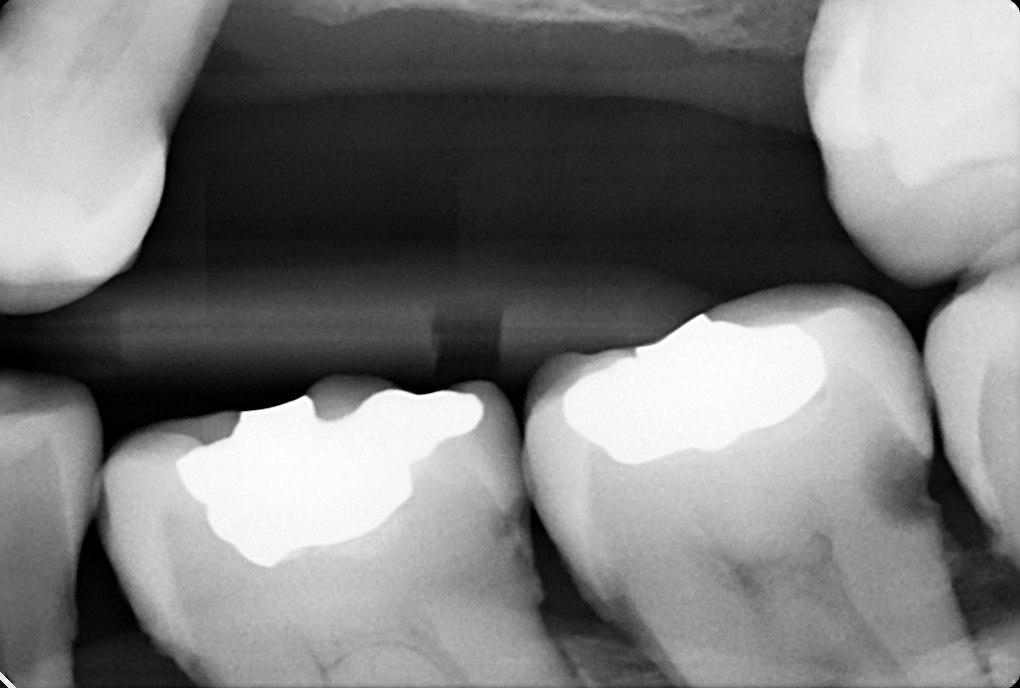

1. What is the condition in the distal surface of the tooth # 4.6?

2 / 30

2. What is the condition in the distal surface of the tooth # 4.7?

3 / 30